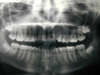

Les radios